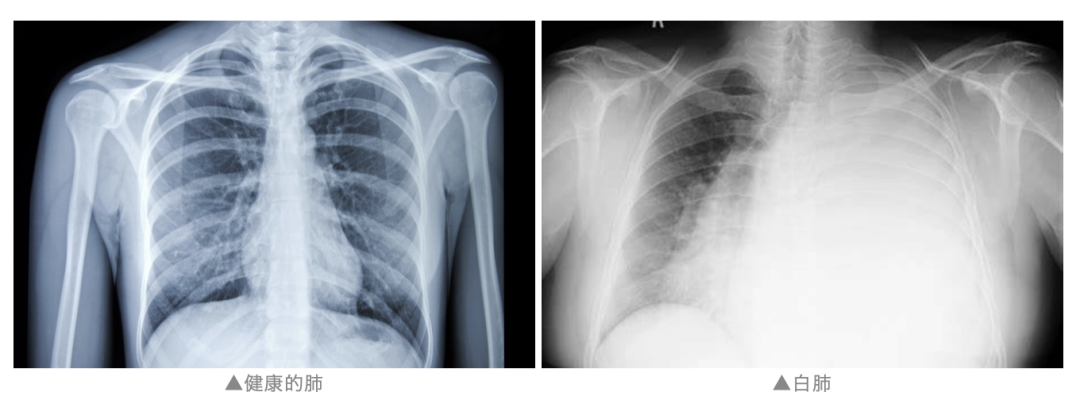

白肺一般是指重症肺炎患者在X线或CT检查下的表现,因一大片"白肺"而得名,医学上也称"急性肺损伤"。

一般来讲肺部炎症较重、渗出液较多,白色的影像区域面积达到70%—80%时,在临床上把它称为白肺。临床上,白肺表现为胸闷、气短、呼吸不畅,白肺患者血氧饱和度低,会导致严重缺氧,白肺的形成一般说明肺部有炎症浸润。

(图片来源于网络)